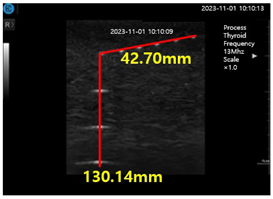

Figure 15a shows ultrasonic gel testing at various time intervals using the ATS-539 phantom. Figure 15b shows the sharpness of the image of the manufactured gelatin soft gel after storing it in alcohol and performing a sharpness test at 1 h intervals for 72 h. The results are presented in Figure 15b. In this paper, the experiment using a soft solid gel did not require IRB agreement. This research on the proposed gelatin soft solid gel showed its functionality to be better than that of ultrasonic gel, including on grayscale, echo, and color. This means that it can overcome the tissue density dead zone to increase high resolution performance. To help imaging accuracy, it is proven that gelatin soft gel, especially the soft solid gel, can replace ultrasonic gel to simplify disinfection and ensure permanent use. Image corrosion testing of gelatin soft solid gel for 30 min is shown in Figure 16a. Ultrasonic gels were tested at different times using an ATS-539 phantom, where the gel was soaked in ethanol for 72 h, as shown in Figure 16b. Afterwards, the gel’s condition was tested again. Finally, Figure 16c measures the imaging resolution of the gelatin soft tissue gel.